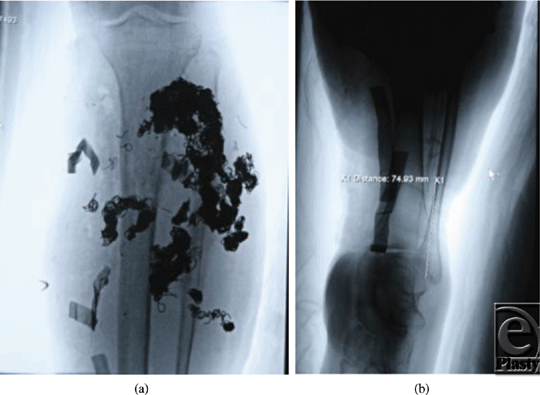

Our patient is a 19-year-old man diagnosed with an arteriovenous malformation of the left lower leg before the age of 10 years from outside of the United States (Figs 1a and 1b). This progressed throughout his childhood and he had become essentially nonambulatory. He was initially treated with local sclerotherapy and embolization in England, starting at the age of 11 years and continuing with 8 additional embolization procedures over the course of 2 years. The embolization procedures were ineffective, and he was subsequently treated with 27 separate interventional radiological coiling procedures in the United States, the latest being performed in early 2010. The patient unfortunately then developed significant tissue necrosis with numerous exposed coil and subsequent deep infection. Skin grafting was attempted but failed, leaving him with a chronic abscess, significant limb edema, pain, foot drop, and severe restriction in his ambulation and activities of daily living (Fig 2). Multiple centers had recommended amputation of the limb.

| Figure 1. Preoperative angiogram demonstrating malformation with multiple coils. |